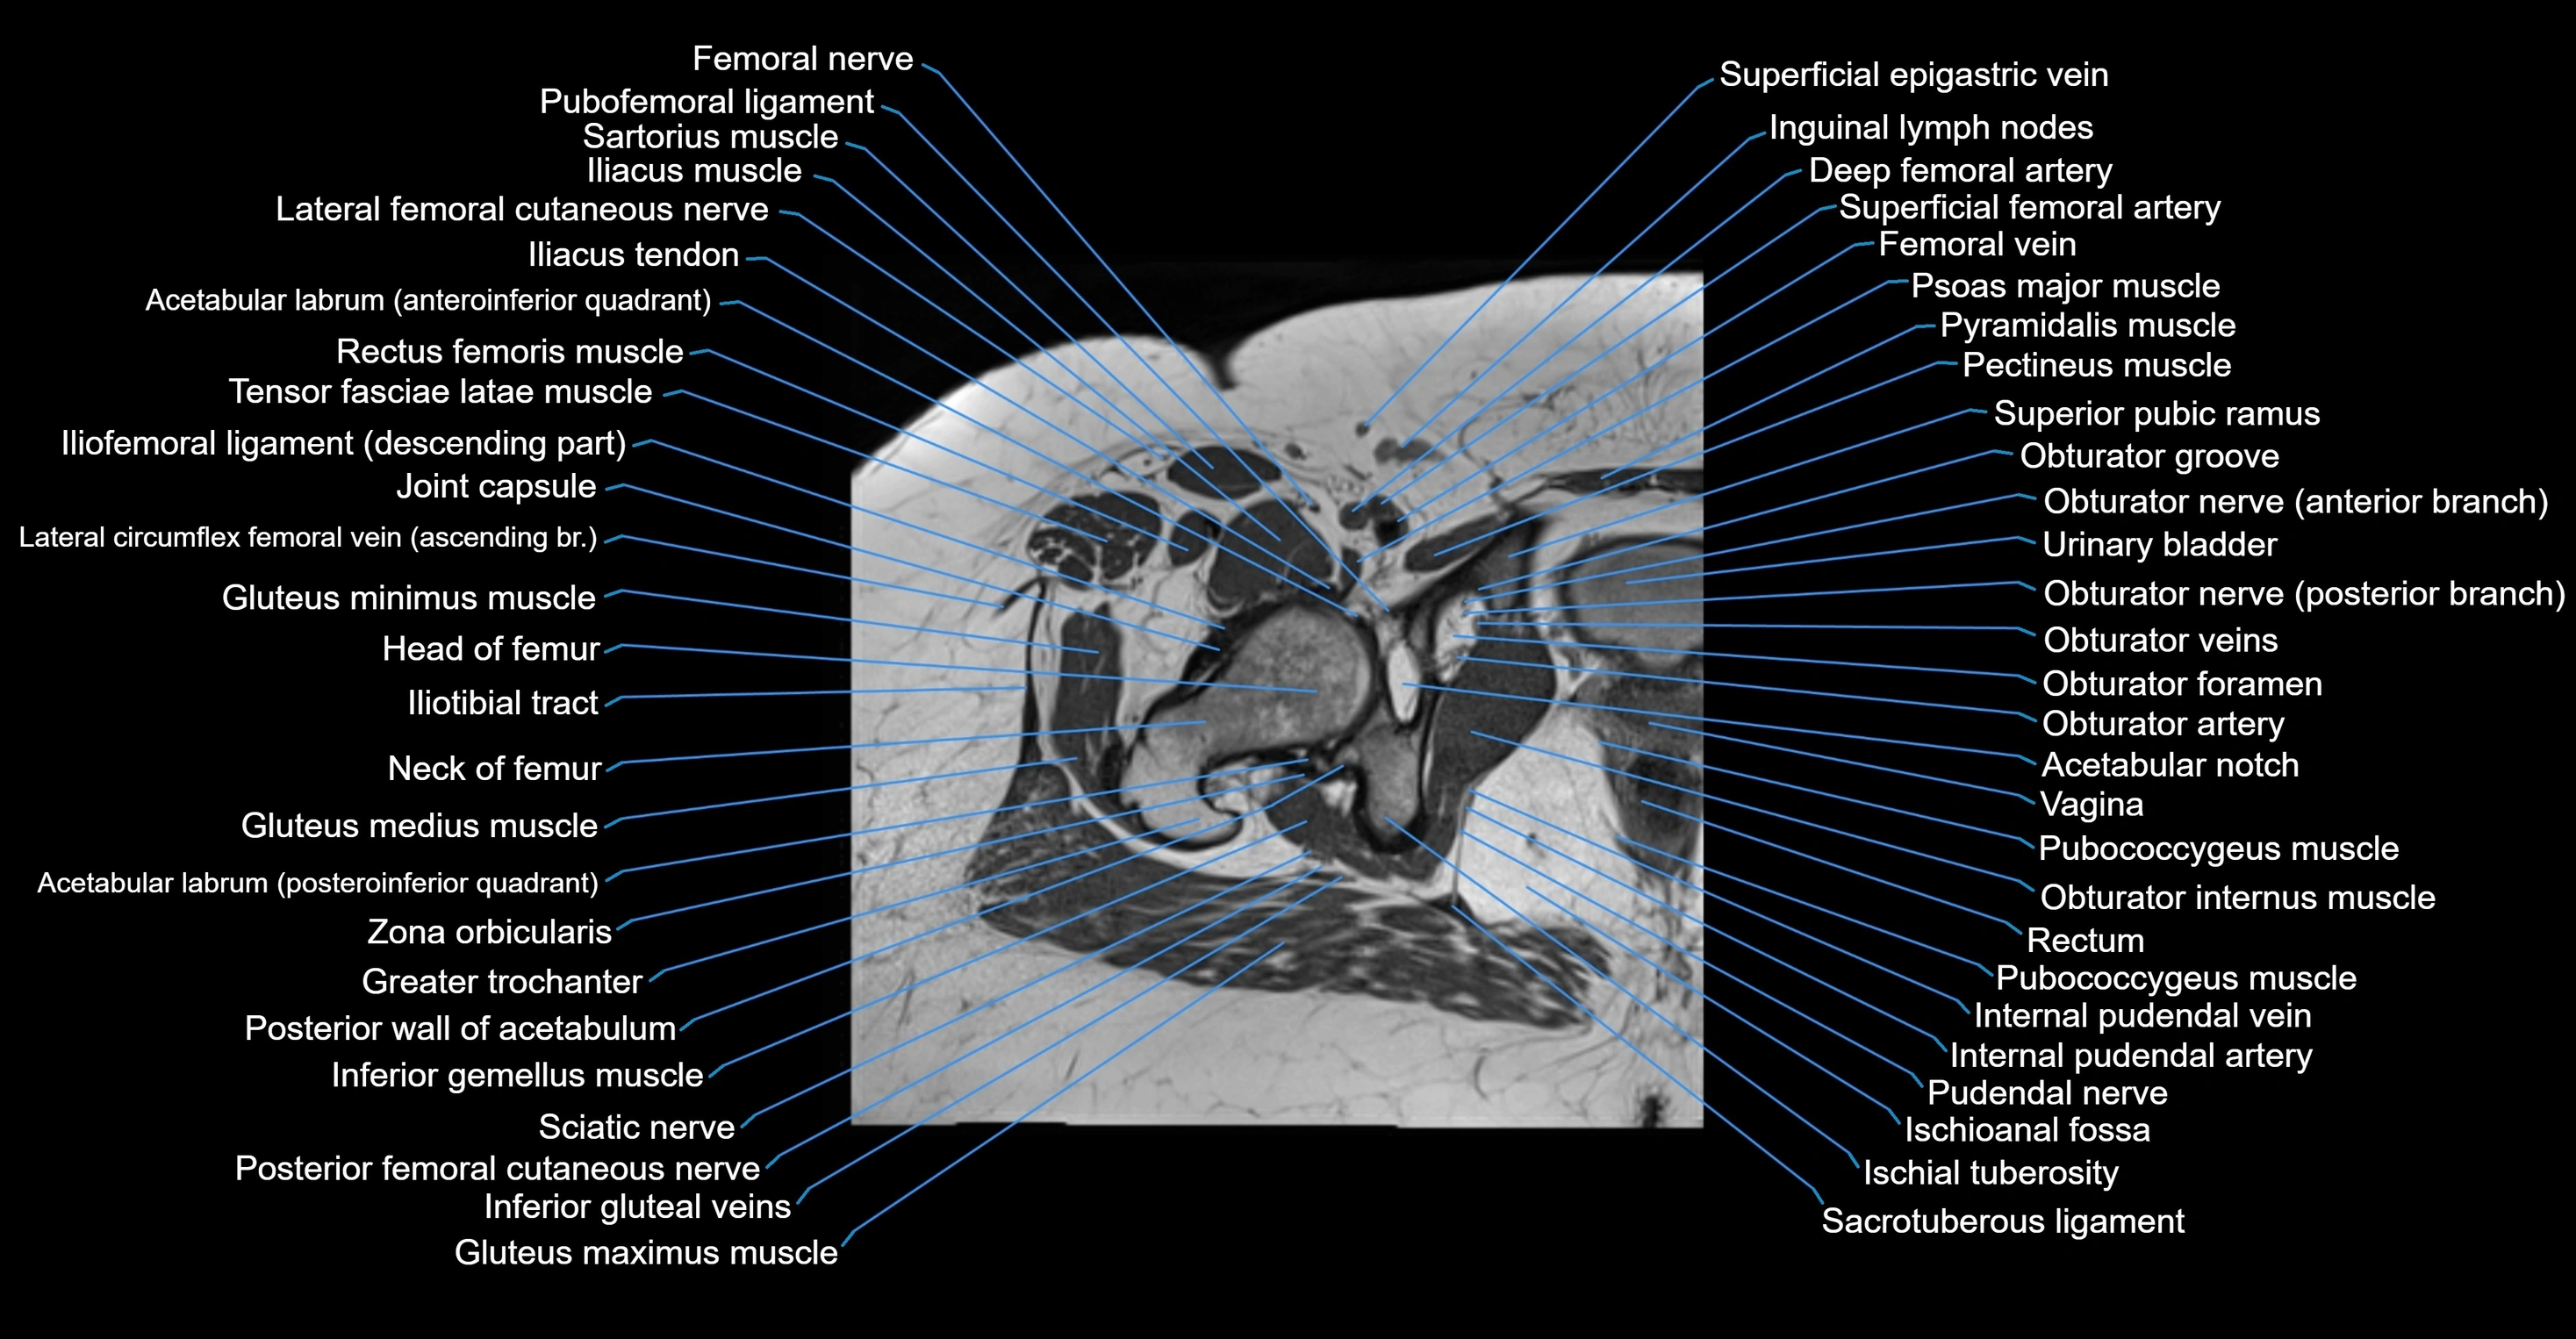

- Acetabular labrum

- Acetabulum

- Femoral nerve

- Gluteus maximus muscle

- Gluteus medius muscle

- Gluteus minimus muscle

- Greater trochanter

- Head of femur

- Iliofemoral ligament

- Iliopsoas muscle

- Iliopsoas tendon

- Iliotibial tract

- Inferior gemellus muscle

- Inguinal lymph nodes

- Neck of femur

- Obturator internus muscle

- Obturator nerve

- Pectineus muscle

- Posterior femoral cutaneous nerve

- Psoas major muscle

- Pubococcygeus muscle

- Pudendal nerve

- Pyramidal muscle (pyramidalis muscle)

- Rectum

- Sacrotuberous ligament

- Sartorius muscle

- Tensor fasciae latae muscle

- Urinary bladder

- Zona orbicularis ligament